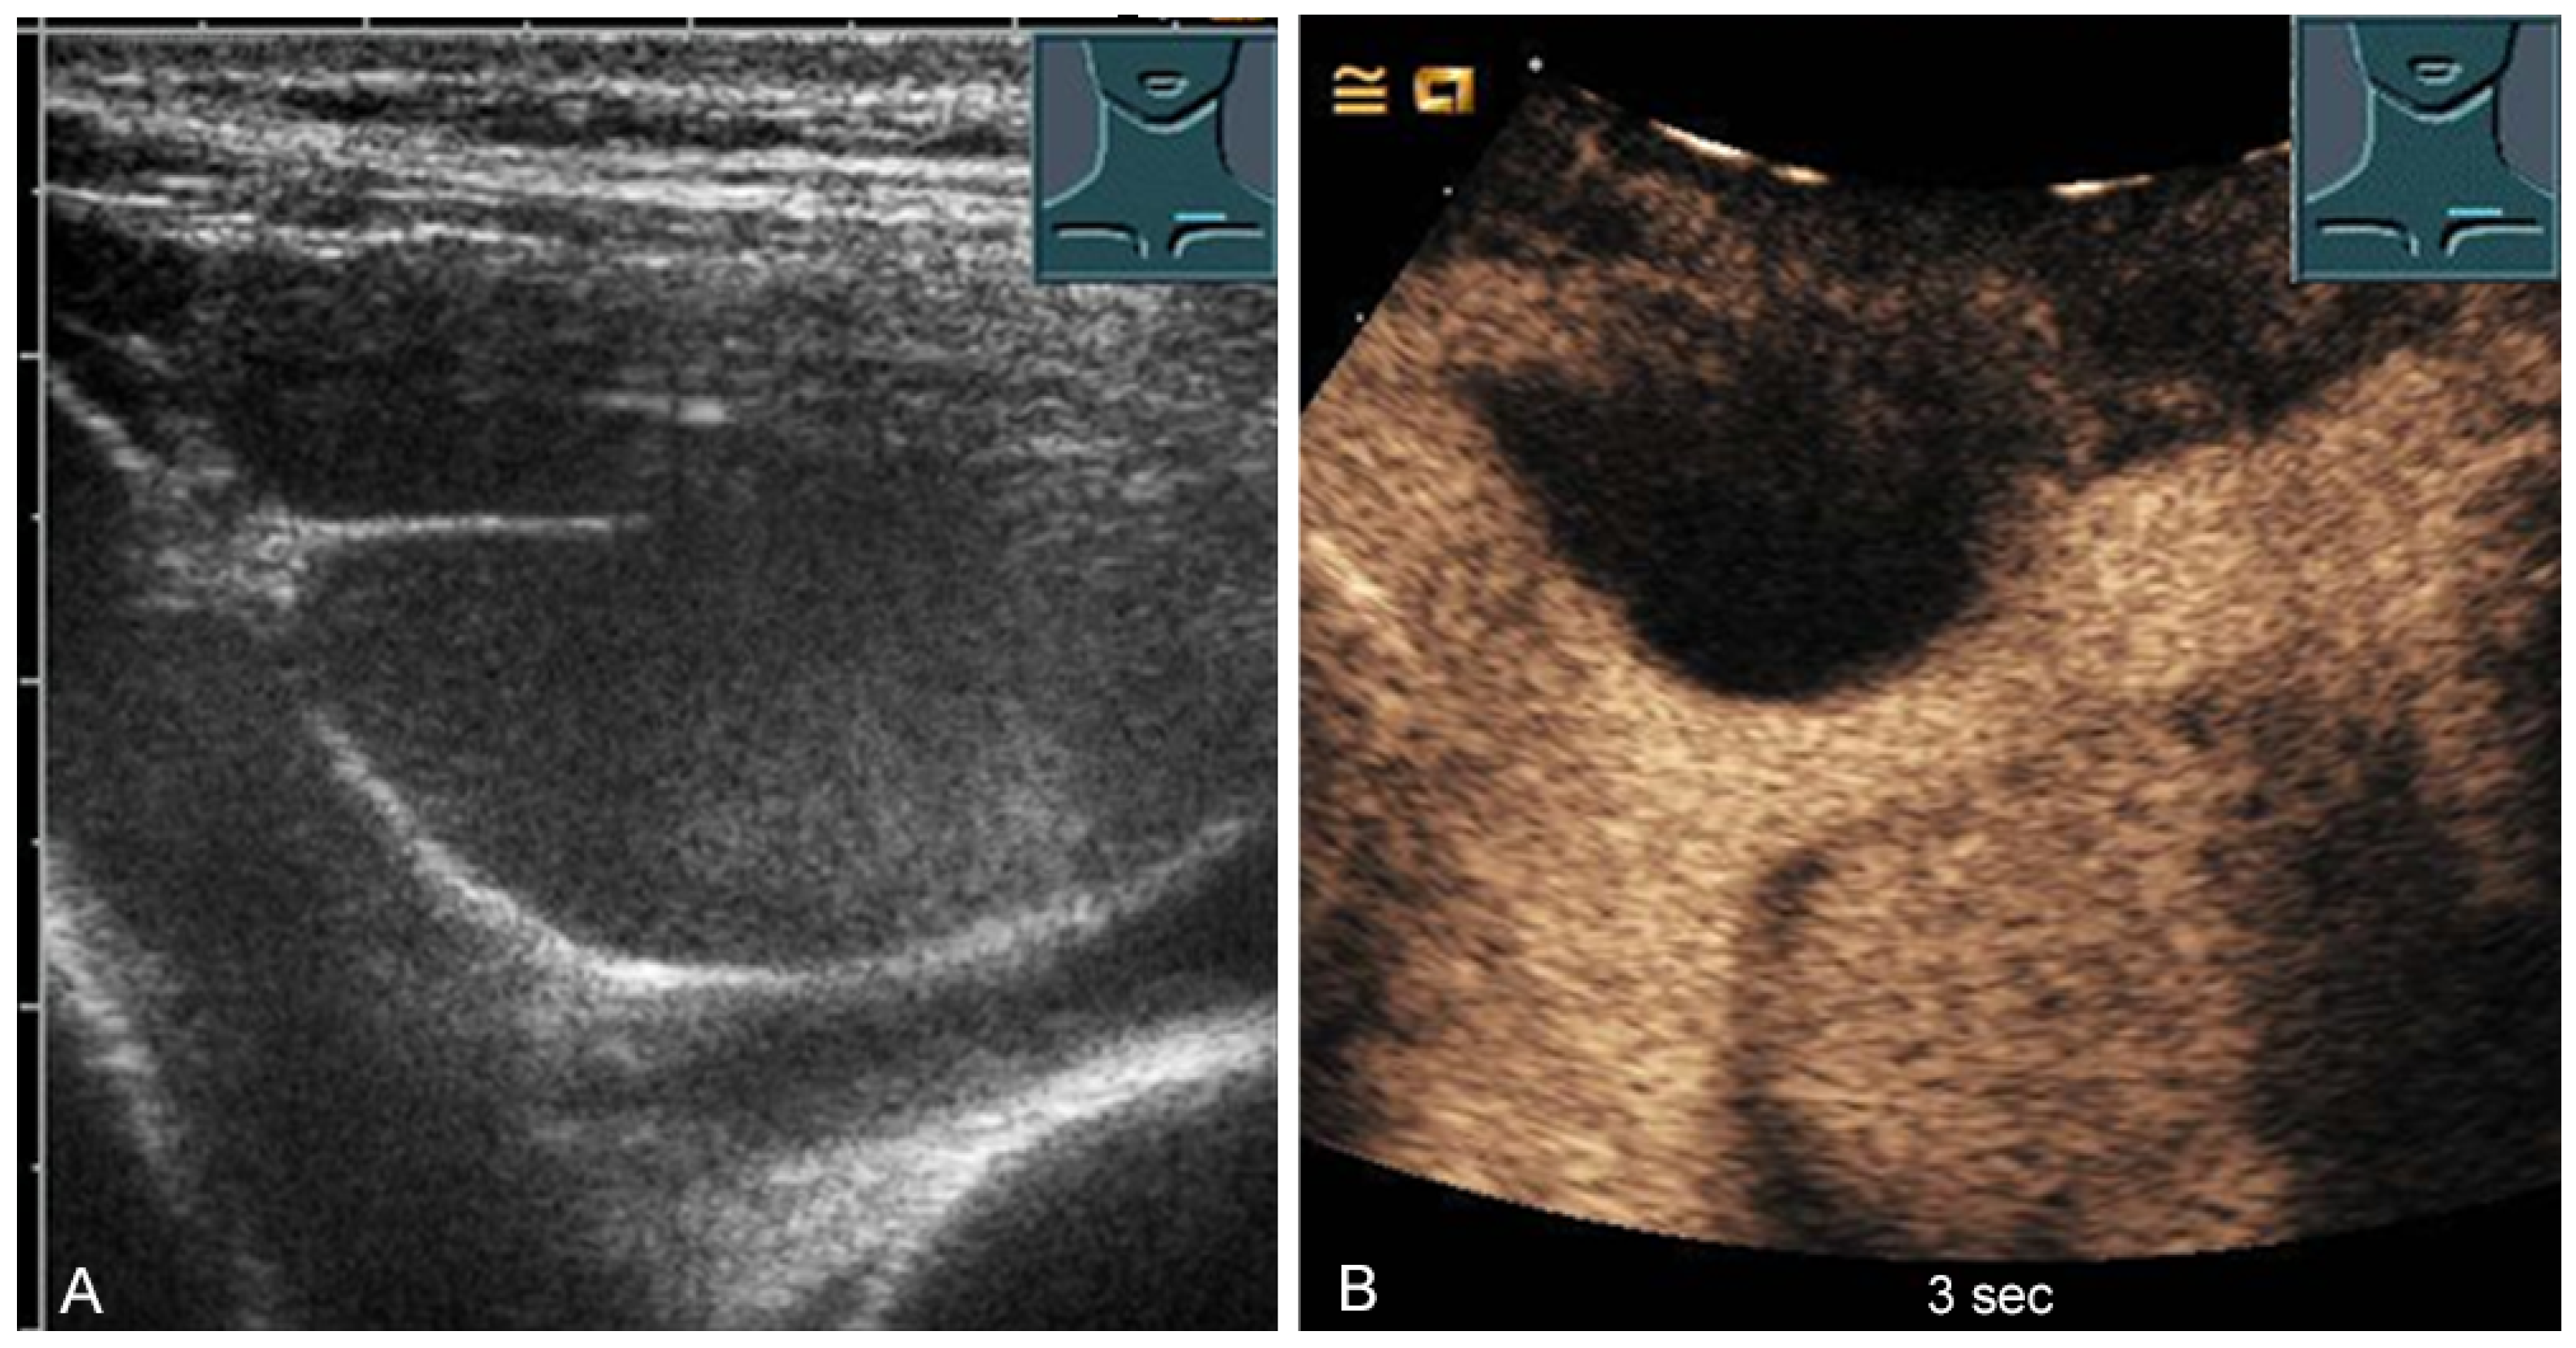

1.6.6. Osteolytic Metastases

Osteolytic metastases show an irregular interruption of the contour of the cortical bone on ultrasound, with varying degrees of inhomogeneously hypoechoic soft tissue. Destruction of the bone results in pathological sound transmission (Figure 11).

Figure 11.

Illustration of different patterns of malignant pathologic rib pathology/rib fractures: (A) minor rib impression in non-small cell lung cancer; (B) complete bony destruction of a rib with visualization of the pleural reflex band in thymic carcinoma metastasis (arrow); and (C) pathologic fracture with a solid soft tissue component in melanoma metastasis.